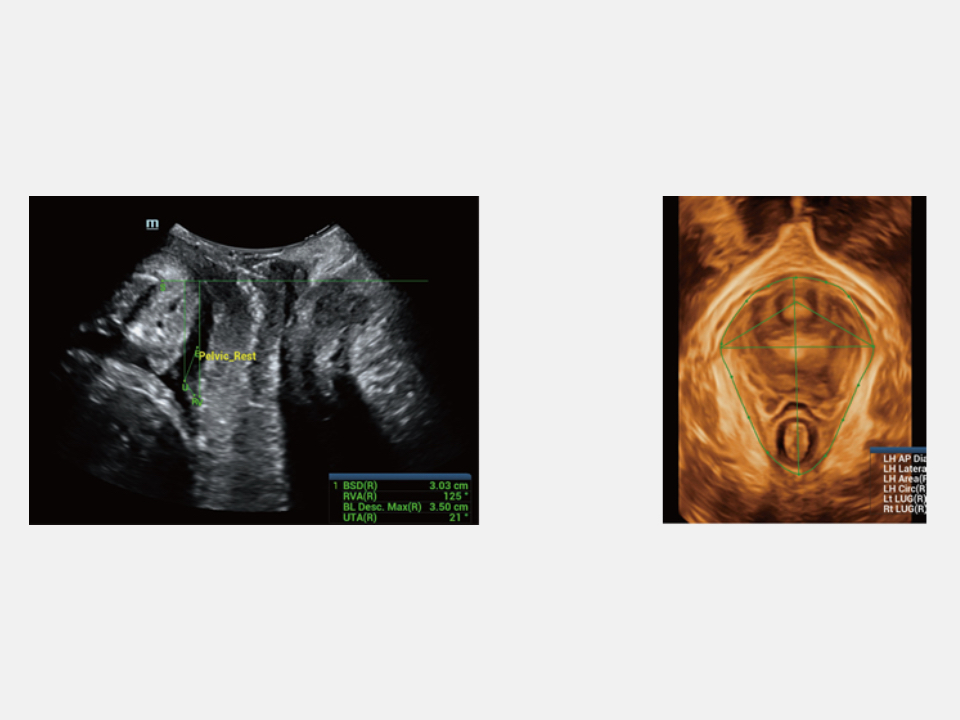

Since the company was founded, Mindray is continuously exploring new ways to improve diagnostic confidence. Powered by the most revolutionary ZONE Sonography? Technology, the ZST+ platform brings ultrasound image quality to a higher level by zone acquisition and channel data processing.

Thanks to the innovative, software-driven ZST+ platform, the Resona series is continuously evolving with the leading-edge technologies to meet the most challenging diagnostic demands in womenŌĆÖs health practice. More importantly, it is designed with the understanding that the wisdom of experts is always precious, and you need more intelligent partner for enhanced speed and confidence. Finally, Resona series with Zone Intelligence provides a total solution to help you with diagnostic confidence, efficiency, and standardization across different diagnostic challenges in todayŌĆÖs demanding and overburden hospital environment.